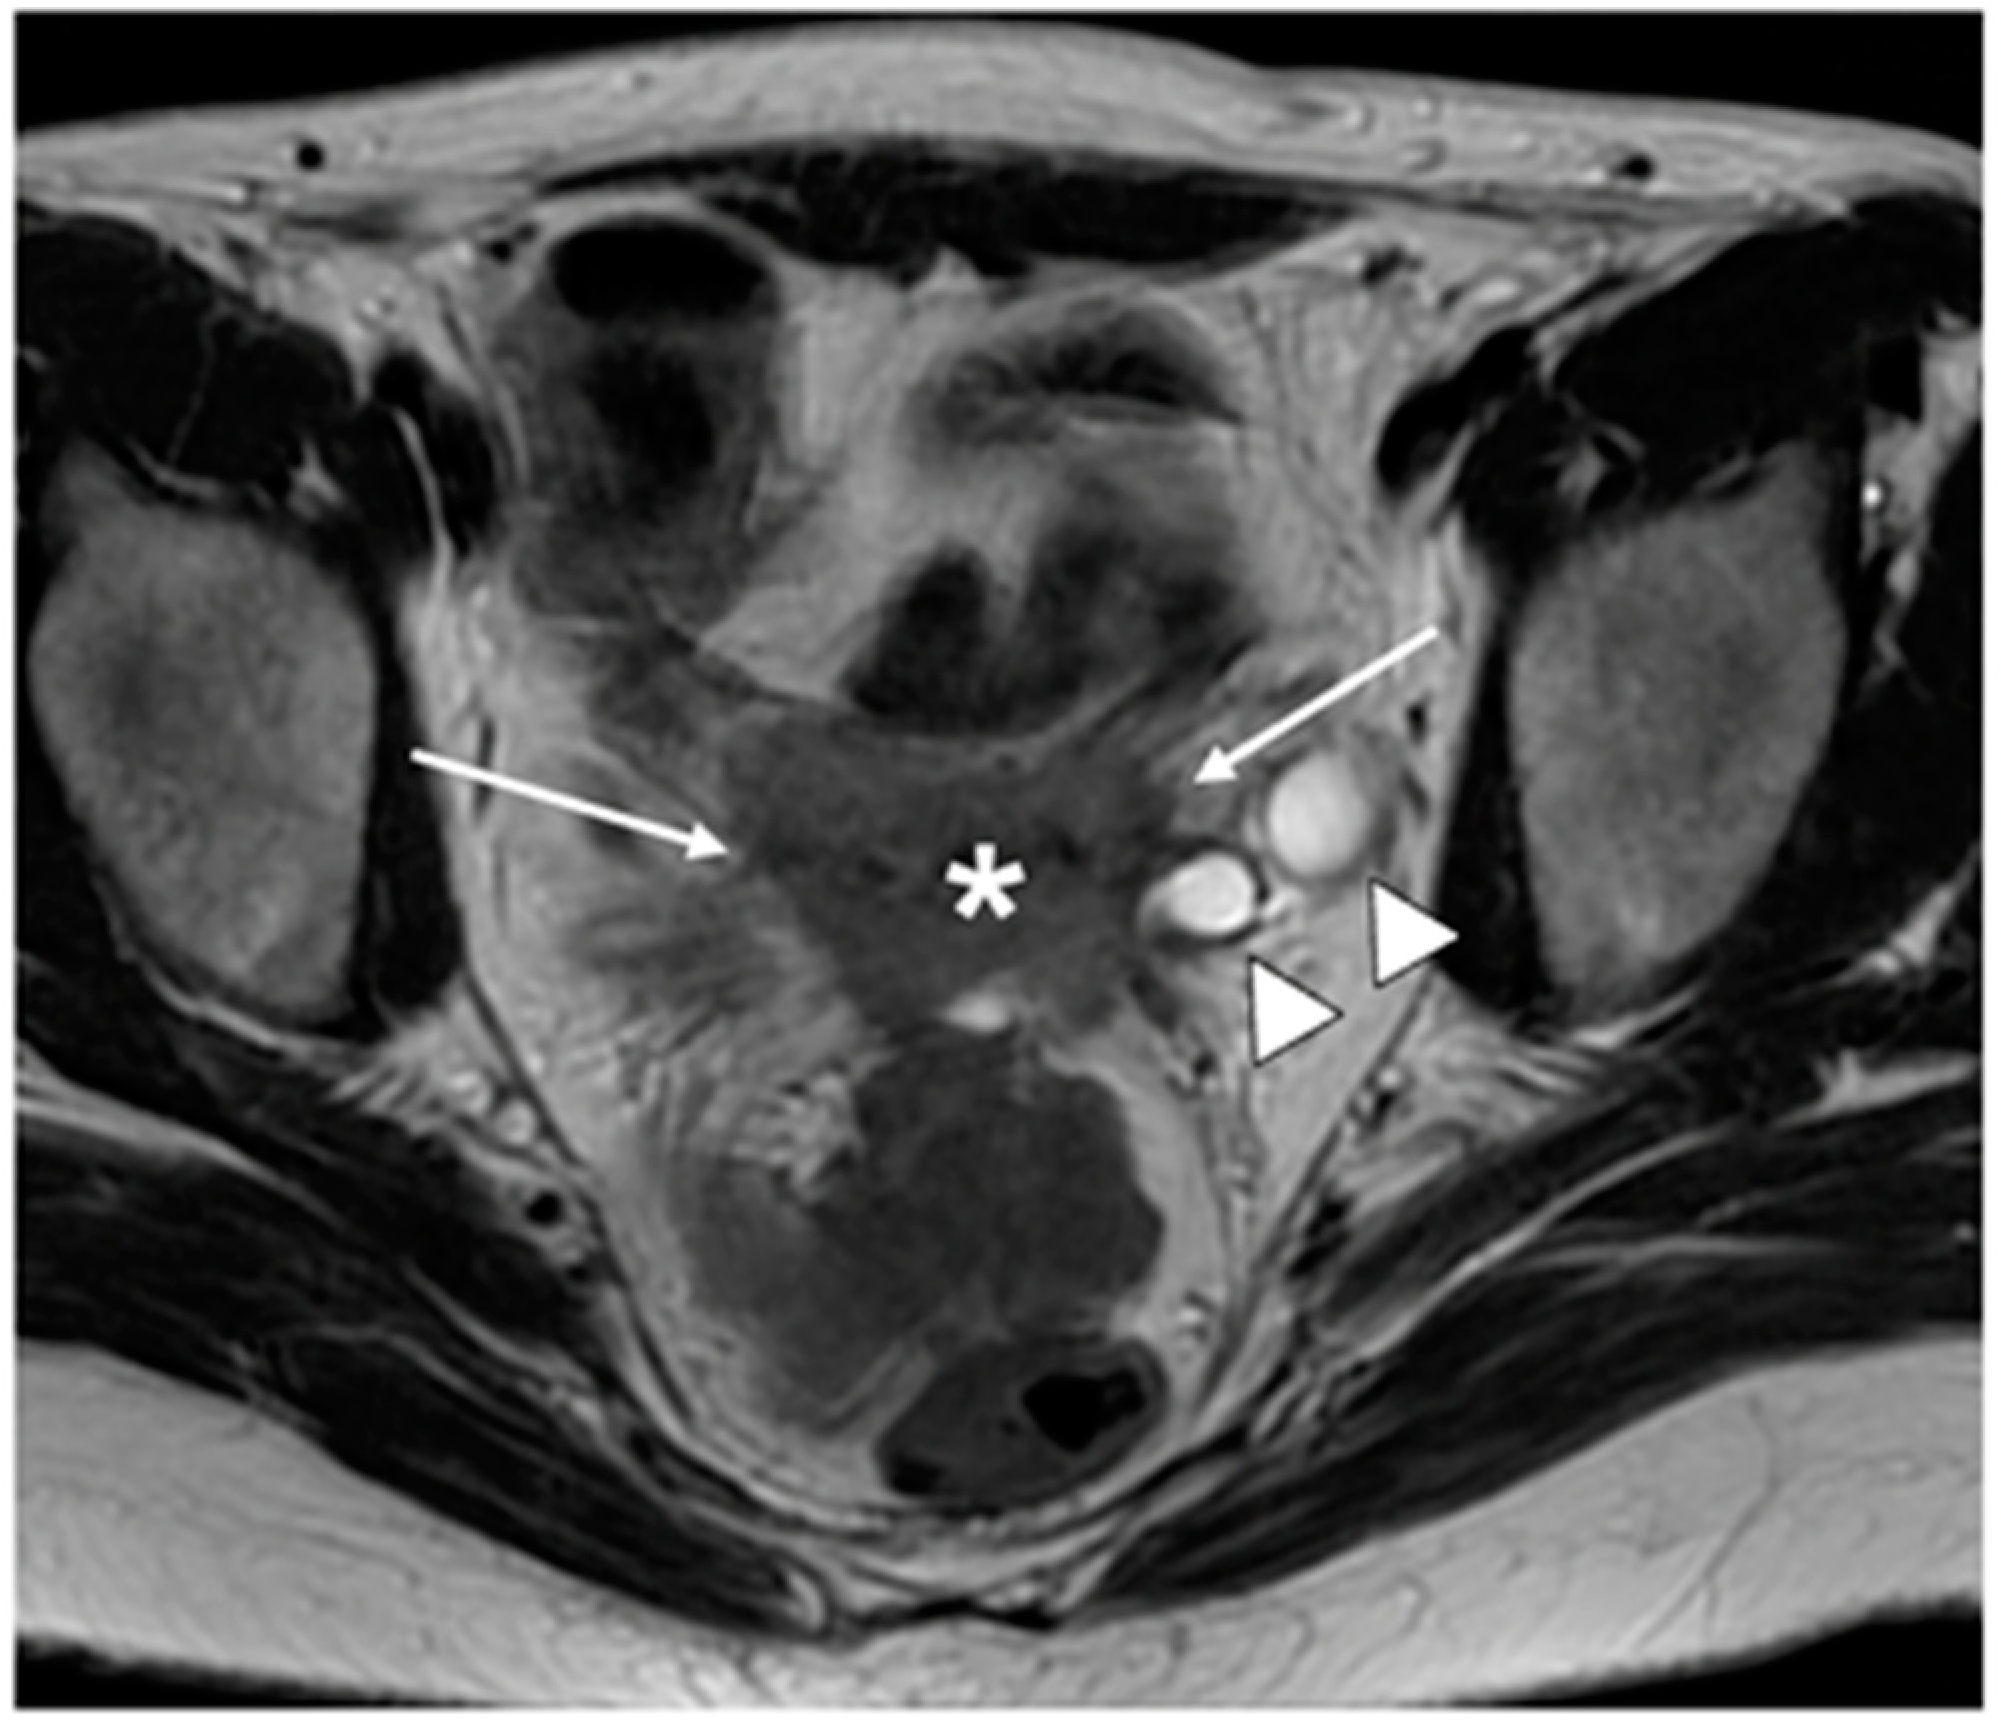

6. FIGO Stage III

- Valentini, A.L.; Gui, B.; Miccò, M.; Giuliani, M.; Rodolfino, E.; Ninivaggi, V.; Iacobucci, M.; Marino, M.; Gambacorta, M.A.; Testa, A.C.; et al. MRI anatomy of parametrial extension to better identify local pathways of disease spread in cervical cancer. Diagn. Interv. Radiol. 2016, 22, 319–325. [Google Scholar] [CrossRef]